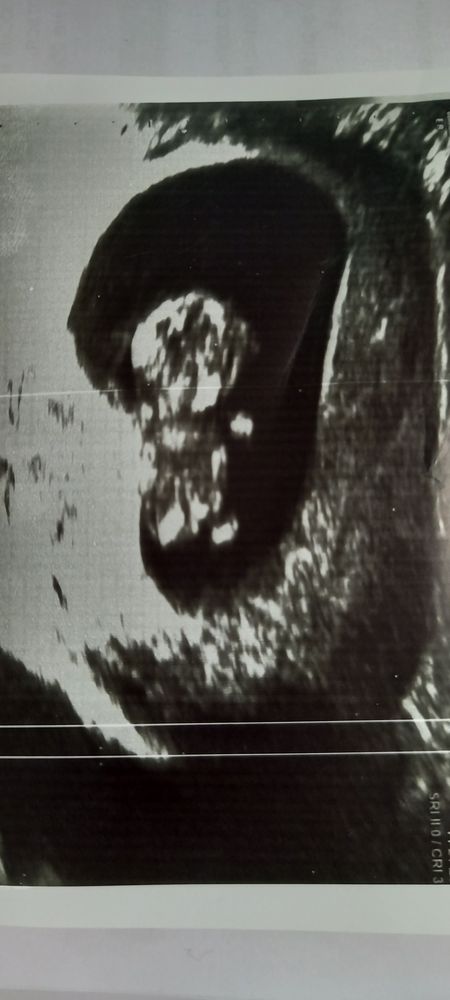

Сходила на очередное УЗИ. Срок 9.5. Малыш хорошо развивается. Проблем никаких врач не видел. Выделения кровянистые прекратились уже неделю как самостоятельно. В общем врач обратил внимание только на то,что длина шейки на УЗИ 2 недели назад была 33мм, сейчас 32мм. А это только 10н. Плод ещё ничего не весит. Ну и как бы намекает,что потенциально возможны проблемы с шейкой. 1.4 назад были роды и были разрывы ШМ в том числе. У кого шейка была не очень длинная изначально? Расскажите получилось или нет избежать ИЦН? Ну и какая тактика была врачебная? Понятно что мониторинг каждые пару недель и тд. Но хочется ваших истории.

Здравствуйте! у меня в 11 недель была 33 мм, потом делали узи на 18 неделе 37 мм. Врач сказала, что если не беспокоят боли, выделения, если зев закрыт...то не стоит чего либо предпринимать если шейка длиннее 25 мм. Но конечно это все индивидуально, я думаю. Мне так сказал врач моя и пока все хорошо)

С начала беременности была 34, потом 32, потом 37, потом снова 34, а вот полторы недели назад 39.

У меня на первом скрининге в 12.6 шейка была 37 мм. Я так понимаю это тоже не входит в нормы, вроде должна быть длиннее, но никто ничего не сказал. Моя врач назначила мне церквикометрию на всякий случай (она ее всем назначает). В 16 недель 32, назначили утрожестан, в 18 недель 33.7. Но мне кажется что мне в 16 недель ее не верно намеряли. Пока врач говорит мониторить. Тоже писала тут по этому поводу. Девочки говорят что до 25 - норм. И ещё нужно чтобы был закрыт внутренний зев, и чтобы сама шейка была не рыхлая. Может у вас такая особенность что она такой длины. Я потом ещё ходила к другому врачу, чтобы проконсультироваться. Она сказала что такая длина может быть обусловлена моей конституцией. У меня рост выше среднего.